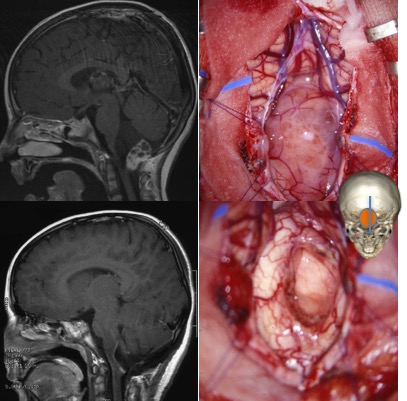

l’abord des tumeurs de la jonction bulbo-médullaire

il s’agit d’un abord médian sous-occipital classique.

l’exérèse peut être grandement facilitée par l’existence de kyste tumoraux qui réalisent parfois un plan de clivage idéal avec le névraxe.

certaines tumeurs sont purement intra-axiales ; lorsqu’elles affleurent à la face postérieure, elles sont accessibles par une incision postérieure médiane similaire à la chirurgie des tumeurs intra-médullaire.

dans les cas d’une tumeur infiltrante (astrocytome pilocytique ou souvent gangliogliome), on doit se contenter de biopsies. en raison du caractère superficiel de ces tumeurs, de leur proximité des vaisseaux (PICA) et de la consistance ferme voire dure, il est souvent préférable de réaliser une biopsie à ciel ouvert que des biopsies stéréotaxiques.